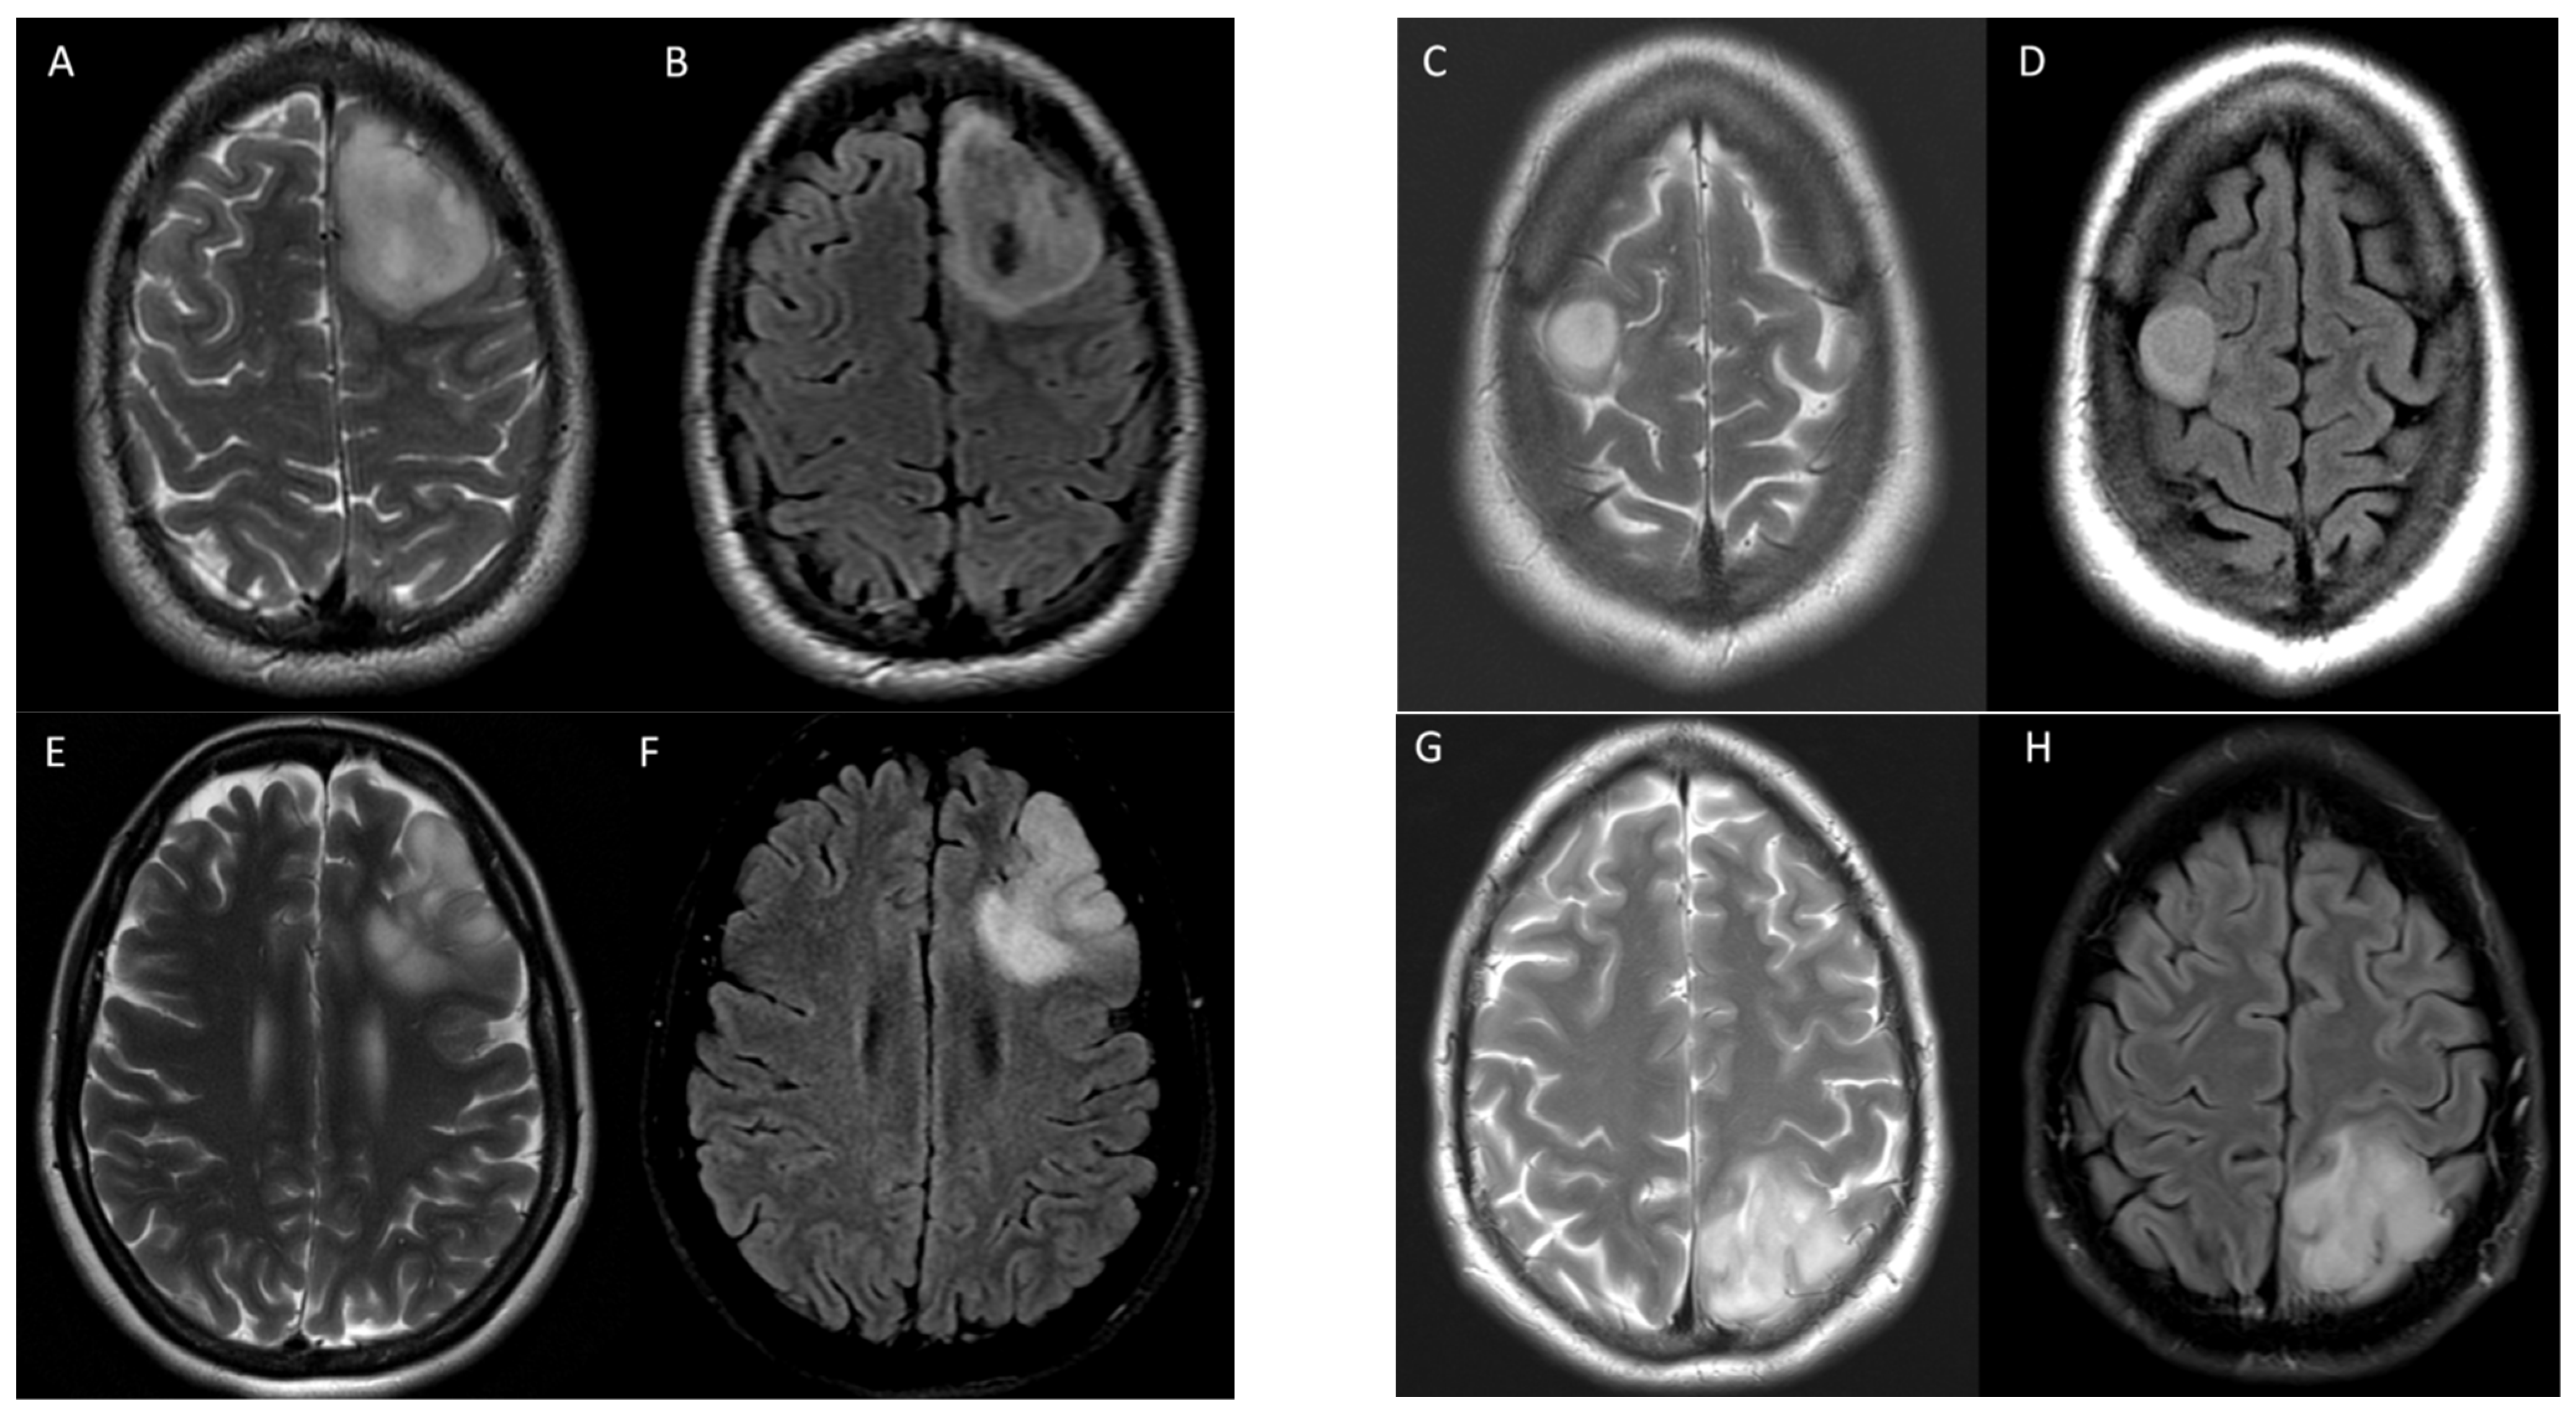

Figure 4 shows an example of two instances where the initial incorrect assignment of the 1p-19q status was correctly changed after using a predictive texture model such as CAT.

Figure 4. Two examples of correct changes made to T2-FLAIR mismatch evaluation with CAT. Axial T2 (A,B) and FLAIR (C,D) images in a 33-year-old male with IDH1 mutant glioma and non-co-deleted 1p/19q. During the initial interpretation, this was read as T2-FLAIR match but during the 2nd interpretation in conjunction with radiomic predicted result, this was correctly changed to T2-FLAIR mismatch. In this case, the heterogeneity of signal in different parts of tumor may have contributed to the initial error. Although there is relative matched signal between (A,C), there is subtle suppression of signal within the lower part of this tumor seen on (B,D) images. Axial T2 (E,F) and FLAIR (G,H) images in a 50-year-old male with IDH1 mutant glioma and co-deleted 1p/19q. During the initial interpretation this was read as T2-FLAIR mismatch; however, in 2nd interpretation in conjunction with radiomic predicted result, this was correctly changed to match. In this case, the prevalence of multiple small cystic components and their suppression on FLAIR images may have contributed to the initial error; however, when comparing (FH), it is apparent that the majority of signal is matched between T2 and FLAIR.